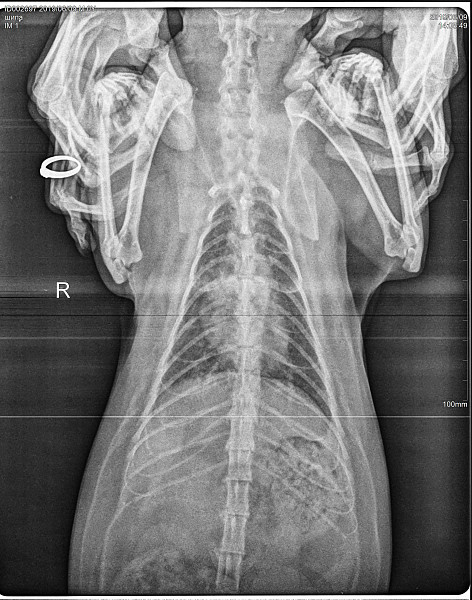

Дыхание животом у кошек